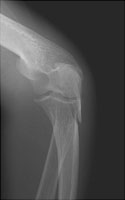

- Click on the image for a larger versionALateral radiograph of the elbow. The typical appearance of an olecranon fracture. The triceps tendon has distracted the fracture fragments.

- Click on the image for a larger versionBOblique radiograph of the elbow. This image also demonstrates the olecranon fracture.